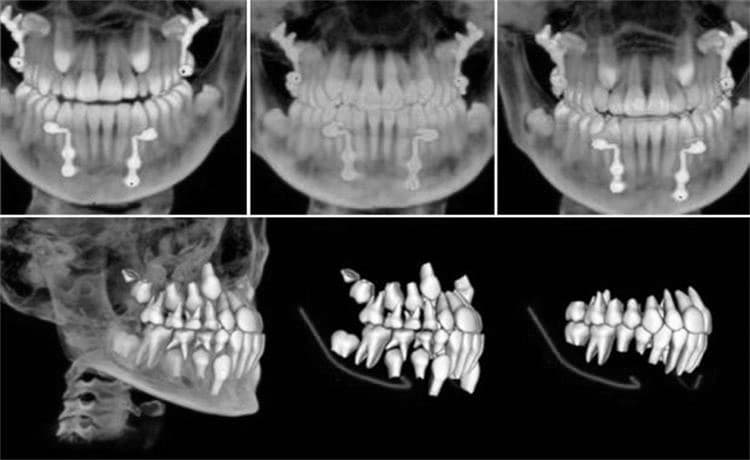

A dental CT scan is a type of X-ray that produces 3D images of the teeth, jaws, and surrounding structures. This technology is particularly useful in surgical planning for dental implants, as it can provide detailed information on bone quality and nerve canals. Unlike traditional X-rays, which only show a flat image of the teeth and jawbone, a CT scan provides a more detailed and accurate picture of the area.

Dental CT scans are necessary for a variety of reasons. For example, they can help diagnose and treat conditions such as impacted teeth, cysts or tumors, bone defects, or nerve canal involvement that could affect treatment. They are also useful in planning for dental implants, root canals, wisdom teeth extractions, and orthodontic treatments such as braces or Invisalign.

The accuracy of the scans allows dentists to identify areas of decay around existing fillings or crowns that might not be visible with traditional radiographs. This helps to ensure that any potential problems are addressed before they worsen and cause further damage. Furthermore, the 3D images produced by the CT scan allow dentists to view the mouth from all angles in order to get an accurate picture of what is going on inside the mouth. This helps them to assess any potential risks associated with various dental treatments and make informed decisions accordingly.